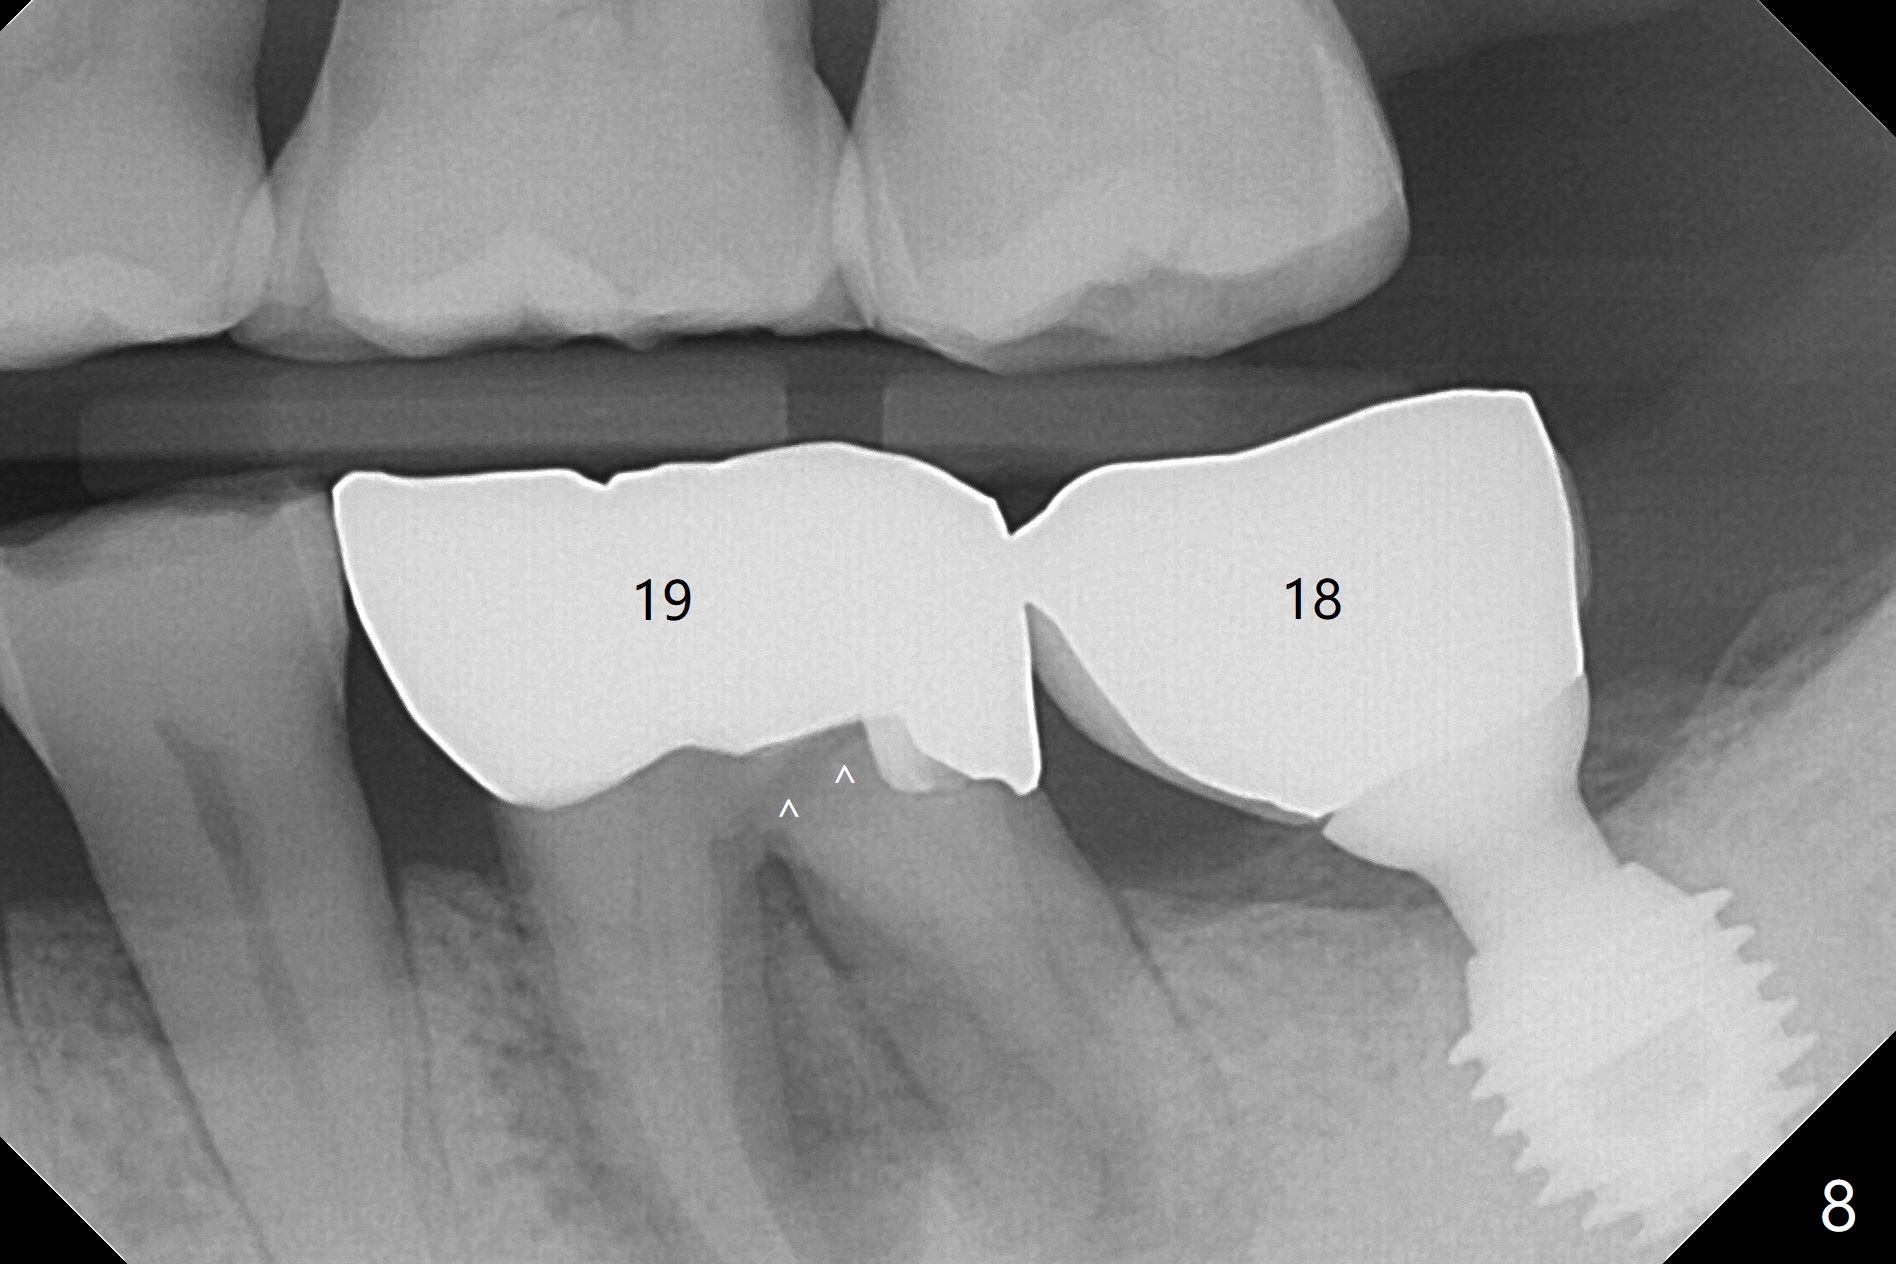

Vertical fracture of the mesial root of the tooth #30 after RCT is associated with bone loss (Fig.00 *). When the mesial portion of the mesial root (M', loose one) is exfoliated, the bone loss resolves (Fig.0). To reduce heat-induced bone necrosis at #19, osteotomy is conducted slowly with copious irrigation with cold saline. Bone density is felt while a 5x10 mm implant is being placed after using cortical tap to the 2nd line of the implant driver. The implant needs to be reverse torqued several times before reaching its final depth (Fig.1 (~50 Ncm)). Since the residual roots are superficially positioned, the immediate implant looks as a delayed one. Although the implant is placed mesial to the septum clinically, its position in X-ray seems to be normal. Because of severe wear and lack of vertical height, a 6.8x5 mm healing abutment is placed. Retention of bone graft (Fig.1 *) is maintained by spreading setting acrylic into the edentulous undercut areas (Fig.2 *). The so called "acrylic dressing" remains in place 3 weeks postop (Fig.8). When it is removed with the healing abutment, the wound heals (Fig.3). Note the limited vertical height. The bone graft placed in the distal socket appears to have been converted to the native bone 3.5 months postop (Fig.4). To reduce severe wear of the natural teeth, the occlusion of the new crown is not heavily decreased (Fig.5). It should be alright considering favorable crown/implant ratio (Fig.6). There is no bone loss 5 months post cementation, although the abutment screw is just retightened (Fig.7). In spite of poor trajectory associated with #18 (Fig.8) and 31 (Fig.7) Bicon implants, the abutments have not been dislodged. For the bruxer, the next implant at #19 with distal root fracture (Fig.8 ^) should be Bicon. The patient complains of food impaction nearly 1 year post cementation. The mesial and distal contacts of #30 crowns are light. When the abutment/crown is removed, there is implant well contamination (food debris). It appears that the previous abutment (5.7x4(2) mm, Fig.6,7) is incompletely seated. When a smaller abutment is placed and torqued at 30 Ncm, it is seated fully (Fig.9 (<: no gap)). New impression is taken. The distal gingival embrasure is larger than the mesial one because of the higher distal crest (Fig.6,7). If there is food impaction distal to the new crown, the distal crestal bone should be removed with lab closure of the embrasure.